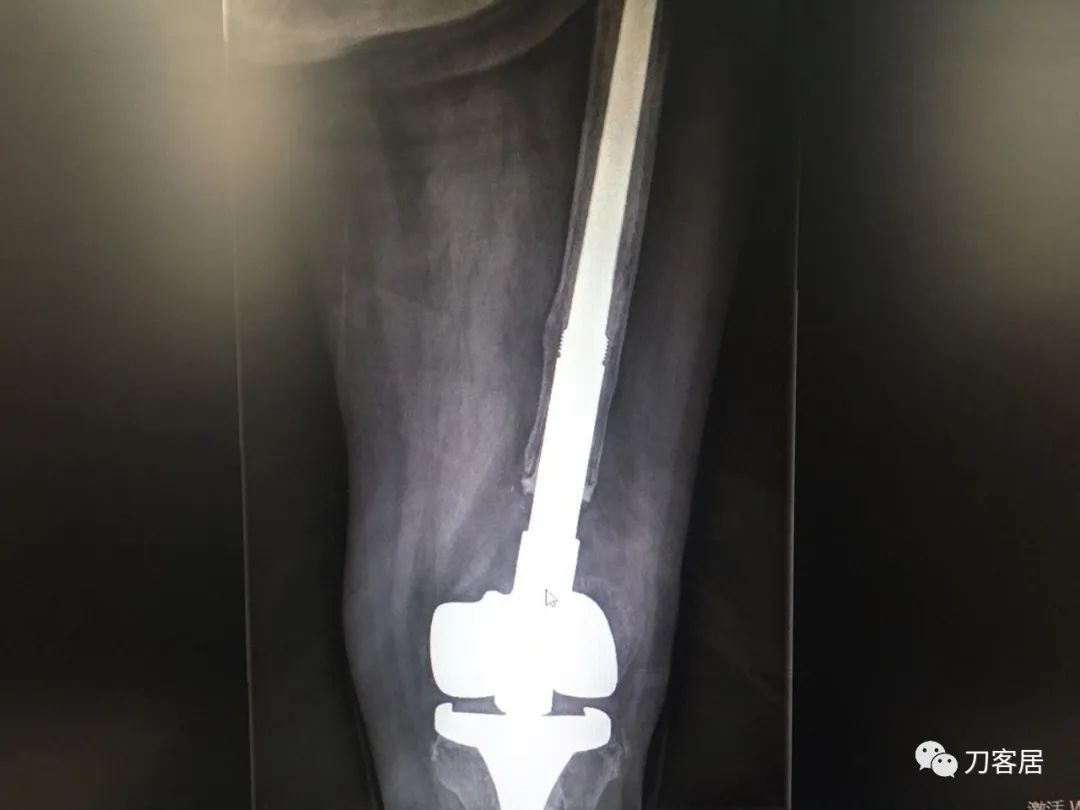

现术后2年摔倒后致假体周围骨折。病人错误的选择,医生错误的治疗,最后导致不好的结局。

风吹麦浪10:25AM分享个病例,女性,67岁,外院手术后2年,现假体周围骨折。

现术后2年摔倒后致假体周围骨折。

刘忠堂,长海关节10:52AM很简单的一例陈旧性骨折,断端硬化并没有太多影响,当时做一个坚强内固定,就可以解决问题,却选择了这样一个方式,2年后出现假体周围骨折,目前也只能做内固定

刘忠堂,长海关节10:54AM锁定钢板,骨折远端半皮质螺钉,周围异体皮质骨板钛缆固定

对我们关节外科医生也很有教育意义。现在治疗很棘手了,首先肯定是复位内固定,要免负重很长时间。

刘忠堂,长海关节11:10AM@云南省罗平县人民医院许永康 异体骨板要长一点

风吹麦浪11:33AM@长海医院刘忠堂固定可能骨质无法长上,刘老师对我来说还是没有把握。